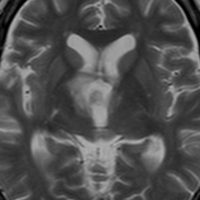

この子の症状は頭痛だけ。両親はなぜ気づかなかったのかと疑問を持ちますが,巨大になるまで症状が出ないこともあるのです。左のCTで腫瘍の周囲にバラバラと白い点状の石灰化があるので診断できます。左の視床下部から発生したクラニオでした。開頭手術しますが超高難易度です,怖いです (┯_┯) 複数回開頭手術になりましたが結果的に全摘出できています (by Dr 山本哲哉)。